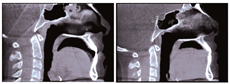

覆盖基本正常,双侧磨牙及尖牙基本中性关系,上切牙切端位置基本不变,下切牙轻度舌倾。开

趋势减弱,垂直向控制较好。矫治后曲面断层显示牙根平行,未见明显牙根吸收。CBCT影像显示上下前牙牙根基本位于牙槽骨中央(图8)。术后关节间隙及髁突骨质未见明显变化(图9)。矫治前后头影测量重叠图(图10)。